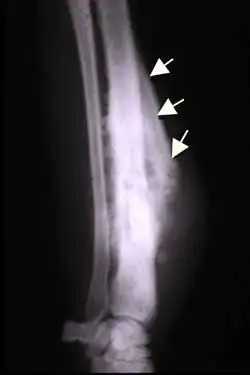

Codman triangle

The Codman triangle (previously referred to as Codman's triangle) is the triangular area of new subperiosteal bone that is created when a lesion, often a tumor, raises the periosteum away from the bone.[1] A Codman triangle is not actually a full triangle. Instead, it is often a pseudotriangle on radiographic findings, with ossification on the original bone and one additional side of the triangle, which forms a two sided triangle with one open side. This two sided appearance is generated due to a tumor (or growth) that is growing at a rate which is faster than the periosteum can grow or expand, so instead of dimpling, the periosteum tears away and provides ossification on the second edge of the triangle.[2] The advancing tumour displaces the periosteum away from the bone medulla. The displaced and now lateral periosteum attempts to regenerate underlying bone. This describes a periosteal reaction.

The main causes for this sign are osteosarcoma, Ewing's sarcoma, eumycetoma, and a subperiosteal abscess.[3][4]